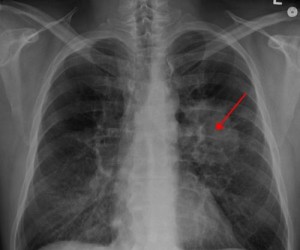

Новый простой тест быстро диагностирует рак легких